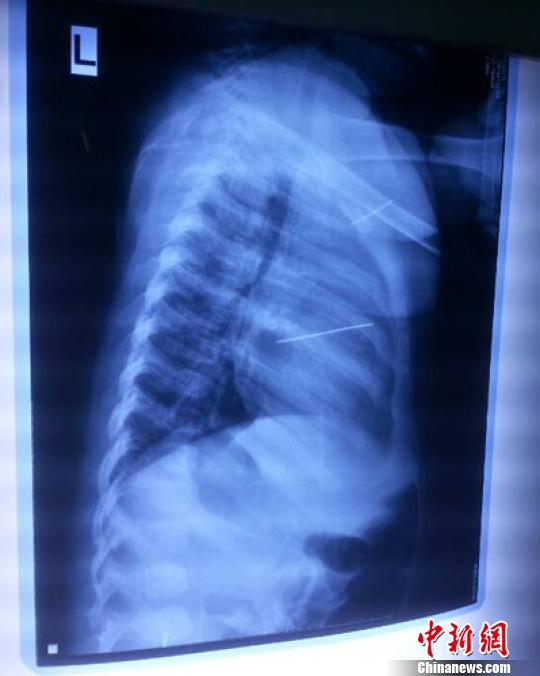

女嬰胸片提示心臟里面扎了一個(gè)縫衣針 蔡迅翔 攝

醫(yī)院胸心外科主任翟波介紹說,1月22日,小患者彤彤因?yàn)榘l(fā)燒抽搐來醫(yī)院就診,常規(guī)檢查時(shí)發(fā)現(xiàn)孩子心臟里面扎了一個(gè)縫衣針。

“第二天上午,我們做了個(gè)緊急彩超檢查,發(fā)現(xiàn)針是從患者右心室表面刺入,穿破室間隔,到達(dá)左心房,中間還有一部分損害到二尖瓣。于23號(hào)下午,我們就做了一個(gè)緊急手術(shù),手術(shù)中發(fā)現(xiàn),這枚針已經(jīng)刺入心臟,沒入了右心室的下面,表面已經(jīng)看不到針了,僅能看到一個(gè)小針眼,還在往外滲血,一點(diǎn)一點(diǎn)的滲,心包腔里面大概有100多毫升的出血,心包上一個(gè)洞,針在右心室表面刺入以后,穿過室間隔,在二尖瓣的上方,進(jìn)入了左心房,在針的四周,有很多纖維沉積物,包繞著這枚針。”翟波說,他們把針取出來以后,測(cè)量了一下,長(zhǎng)度大概是五厘米,同時(shí)發(fā)現(xiàn)這個(gè)針給患者左心房的后壁造成了一定的損傷,左心房的后壁已經(jīng)損傷了三分之二,還剩下有左心房的外膜,很薄的一層,如果這一層再破的話,這個(gè)孩子將會(huì)引起大出血,很快就會(huì)死亡。